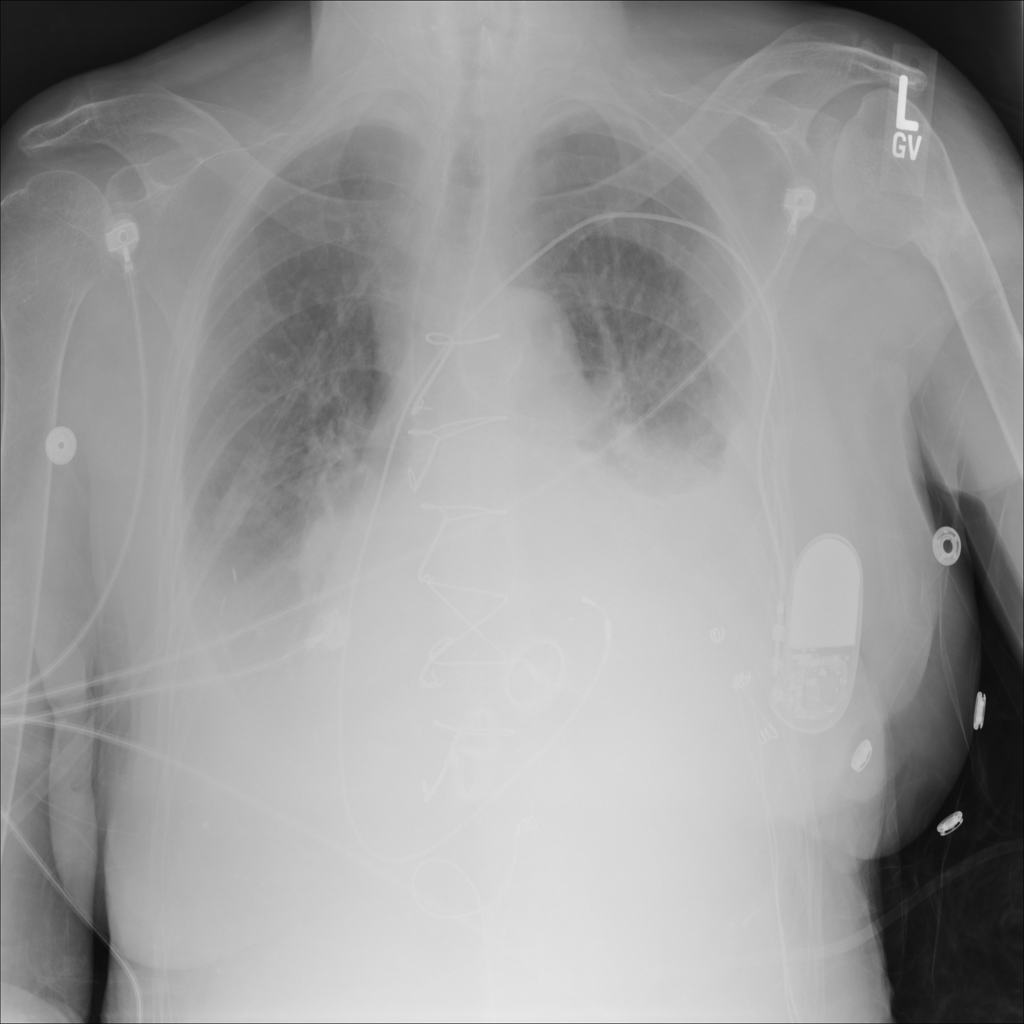

PAT-C0E5 · IMG-008Effusion

PAT-C0E5 · IMG-008

AP